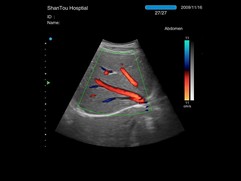

• Disponible opciones de Doppler Pulsado y Color Doppler

Opción de Mapeo de Flujo a Color (Color Flow Mapping) :